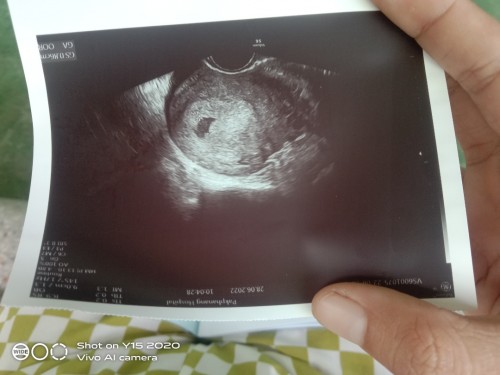

ฝากครรภ์6วีคเจอแค่ถุงน้อยๆเองคะนัดอีกที4สคบ้านไหนฝากครรภ์6วีคบ้างคะ

ฝากตอน6w6d ค่ะ ซาวด์หน้าท้องไม่เจอน้องเหมือนกันค่ะต้องซาวด์ทางช่องคลอดถึงเจอ